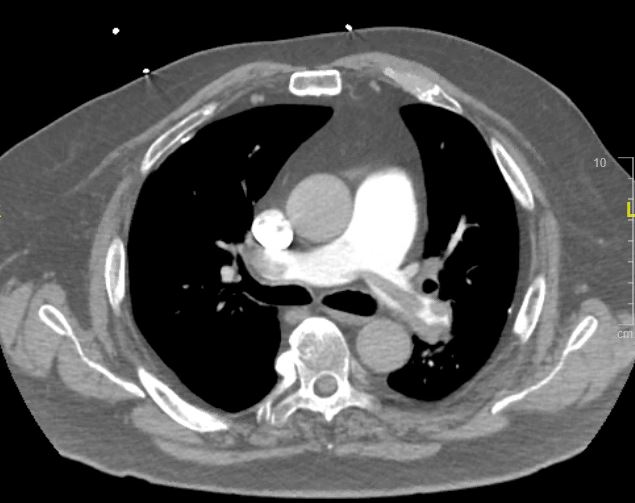

CT chest:

CT chest interpretation: saddle pulmonary embolism

CT chest: Evidence of RV strain. Note RV is larger than LV.